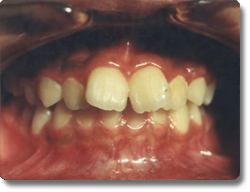

对于儿童及成人的牙齿排列不及,采用方丝弓固定矫正技术治疗儿童及成人的各类牙齿不齐。对于替牙期及恒牙牙列早期的骨性Ⅲ类错颌即“地包天”,采用固定快速扩弓,同期应用面具式前方牵引器,牵上颌前移,对牙面畸形进行矫形治疗,不仅治疗牙列不齐,同时矫正面部畸形,促使面部正常生长发育。